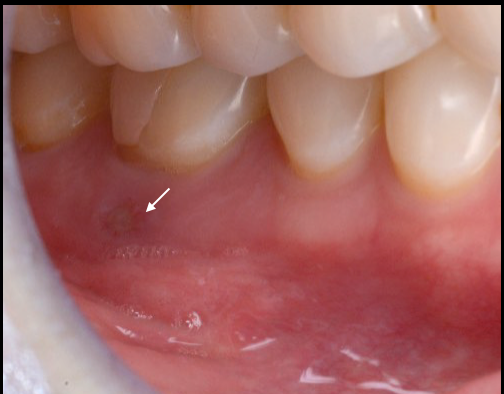

上唇の腫脹を認め、CT検査にて根尖部に嚢胞様透過像を認めた。左上の前歯が不自然に大きく噛み合わせが強くなっていたことがフレアアップの一因と考える。精密根管治療を行い、感染経路を遮断したのち歯根端切除術にて嚢胞を摘出した。

治療中